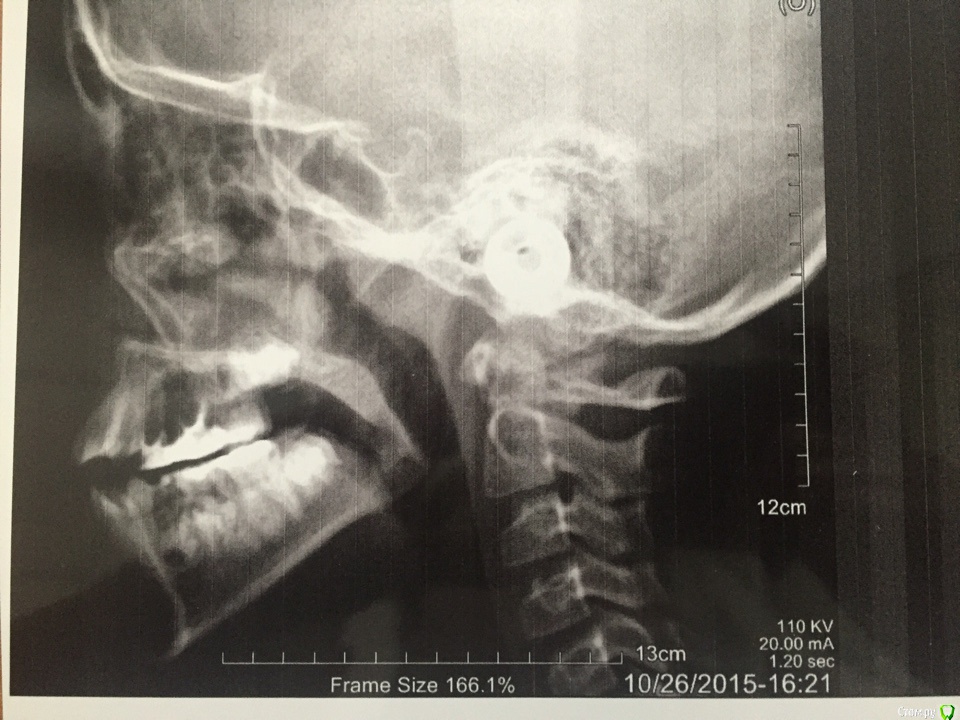

Дорогие коллеги, пожалуйста помогите определится с планом лечения. Пациенту 10 лет, отсутствуют зачатки 15 14 24 25 зубов.

Верхняя челюсть отстает в развитии.

Марат, с трг что -то сомнения. По трг нет контактов между антагонистами вообще и открытый прикус во фронтальном отделе , а по фото все выглядит не так, может ребенок во время снимка открыл рот ? Поэтому трг не информативна.по фото боковых не видно отделов , но клыки по первому классу . Не могу сказать,что верхняя челюсть отстает в развитии. Но трг я бы переделала.